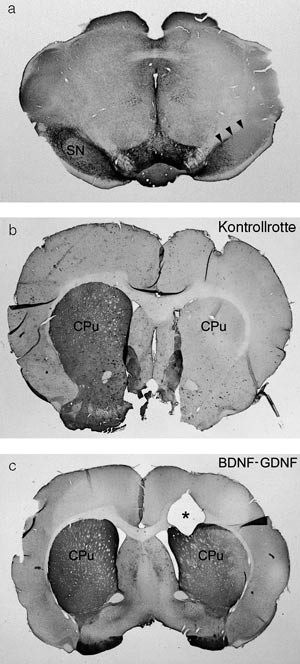

Immuncytokjemiske studier med antistoff rettet mot tyrosinhydroksylase viste bortfall av dopaminerge celler i substantia nigra hos samtlige dyr. Gruppen med kombinasjonsterapien GDNF-BDNF hadde betydelige flere resterende fibrer i terminalområdet (striatum) enn kontrollgruppen (fig 1). Tilførsel av vekstfaktorer førte også til en proliferasjon av subventrikulære celler, som anses for å være den viktigste populasjon av endogene stamceller i den voksne hjernen. Prolifererende celler ble observert i en migrerende strøm av celler lateralt for infusjonsstedet hos vekstfaktorbehandlede dyr, mens det ikke var migrasjon av de samme cellene hos kontrolldyrene (fig 2). Cellene uttrykte både Ki67 og nestin, noe som tydet på at de var aktive progenitorceller. Siden de var negative for både gliale (GFAP-merking) og modne nervecellemarkører (Neu-N-merking), er det uvisst hvorvidt de vil utvikle seg til modne celler.

All animals (rats) were subjected to selective destruction of the dopamine-producing cells in substantia nigra. The rats were divided into three groups. Two groups received intracerebral treatment with either glia-cell derived neurotrophic factor (GDNF) or a combination of brain-derived neurotrophic factor (BDNF) and GDNF. The third group acted as untreated controls and were given sterile saline. The growth factors were infused directly into the brain by an osmotic pump over a period of 28 days. Brain sections taken from all three groups were evaluated by immunocytochemistry.

Dyrene ble inndelt i tre grupper (seks rotter i hver), hvorpå alle ble utsatt for selektiv ødeleggelse av de dopaminerge cellene i substantia nigra. Gruppene ble behandlet med henholdsvis saltvann, GDNF og GDNF-BDNF. I forsøkene ble saltvann eller vekstfaktor infundert direkte i hjernevevet ved hjelp av osmotiske minipumper, lokalisert subkutant, med et kateter koblet til en kanyle som ble plassert stereotaktisk i det aktuelle området i hjernen (striatum). Implantasjon av osmotiske minipumper ble foretatt samme dag som lesjonene ble laget ved injeksjon av 6-OHDA. Vekstfaktorene ble infundert over en periode på 28 dager. De osmotiske pumpene har den fordelen at de gir fra seg kontrollerte mengder, men det er begrensninger både når det gjelder diffusjonsdistanse og varighet av behandling. Motorisk test ble utført ved å injisere apomorfin systemisk. Slike dyr, men ikke friske rotter, roterer (går i ring) når de tilføres apomorfin. Antall rotasjoner per minutt ble målt hos rotter behandlet med 6-OHDA og vekstfaktorer og sammenliknet med antall rotasjoner hos rotter behandlet med 6-OHDA og saltvann (kontrollrotter). I hver gruppe ble seks dyr testet.

The two groups of rats that received growth factor infusion displayed a significant improvement in their motor behaviour compared to control animals. Immunocytochemistry studies demonstrated that the group receiving a combination of GDNF and BDNF had an increased number of surviving active fibres in the dopamine system striatum in comparison to the control and GDNF groups. In addition the infusion of growth factors resulted in a proliferation of subventricular cells in the basal ganglia.